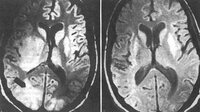

Toxoplasmose

Ressonância nuclear magnética pré e pós-tratamento: cérebro da toxoplasmose no sistema nervoso central

Do acervo de Rima L. McLeod, MD; uso autorizado